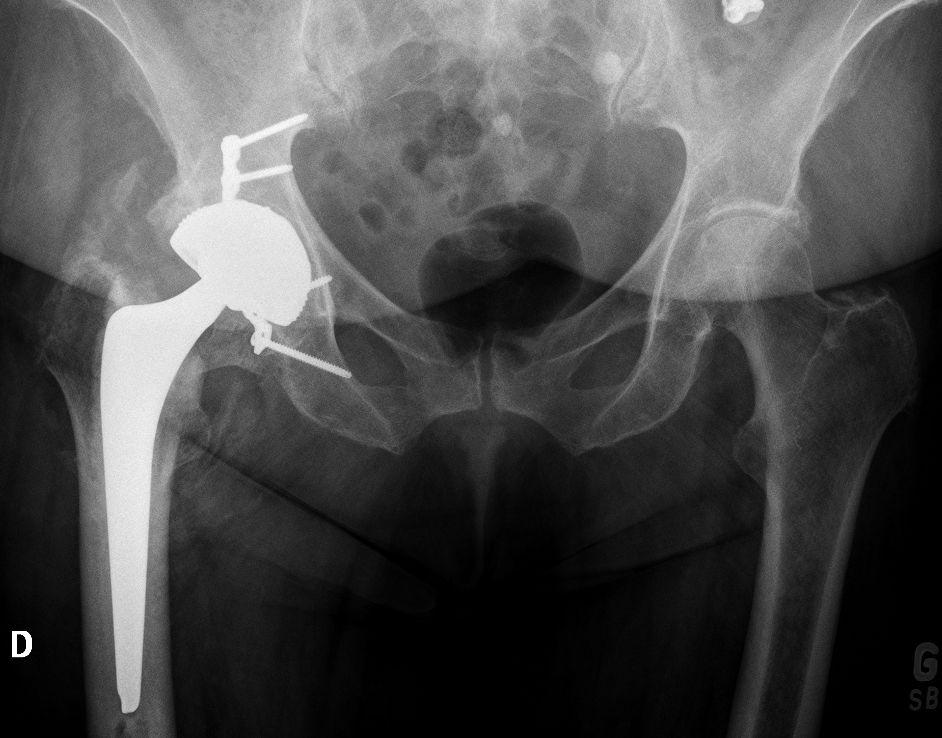

Dislocation is one of the leading causes of THA revision with a variable incidence in the literature. However, calculating the exact rate is a complex matter as closed reductions may remain undetected. Hermansen et al. sought to find the true cumulative incidence of dislocation in 30,000 THAs in the Danish registry and reported a rate of 3.5%[11]. The primary arguments in favour of using an LDH are a wider impingement-free range of motion and a reduced risk of dislocation due to increased jump distance and the larger head volume to displace (Figure 6).

Zijlstra et al. analysed 160,000 THAs from the Dutch arthroplasty register and found that the cumulative risk of dislocation was significantly higher in 22–28mm heads (1.1%), compared to >36mm heads (0.5%)[12-14]. In our experience of more than 3500 CoC LDH THAs implanted since 2011, we encountered five (0.14%) early postoperative dislocations. Four were successfully treated with closed reduction, and one had recurrent dislocations requiring revision surgery. Once instability is of lesser concern, leg length adjustment and femoral offset restoration can be performed with more ease (which helps to achieve goal #1). Using intraoperative measurements or computer/robotic assistance, the surgeon can focus on anatomy restoration without the fear of instability. Knowing that patients would prefer a shortened leg to an elongated one, we favour a shorter one when in doubt between two head lengths.

Using an LDH THA allows unrestricted movement after THA, for all types of surgical approaches. Vendittoli’s group in Canada does not impose any postoperative ROM restrictions for the posterior surgical approach, as it simplifies the patient education process, boosts their confidence during rehabilitation, and facilitates bilateral procedures[15,16]. LDH monobloc DM is especially interesting for many older women with large thighs and a small acetabular cavity (<50mm, Fig. 7).

In these cases, standard bearing diameters are prone to instability. With an LDH, a DM design provides optimal implant stability for these not-so uncommon patients. Moreover, with LDH we do not impose any activity restrictions in the long term. LDH CoC THA offers a major benefit for many active individuals since they can return to their regular jobs (e.g. plumber, roof worker, police officer, fireman) as well as for those who want to practice sports like rock climbing, kayaking, water skiing and martial arts.